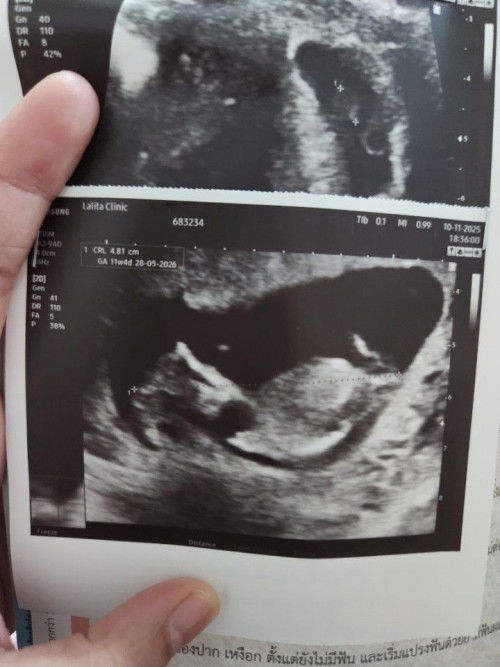

เมื่อวานไปหาหมอซาวด์ท้องเห็นไม่ชัดคุณหมอเลยใช่วิธีสอด เห็นชัด ได้ยินเสียงหัวใจ 6สัปดาห์ ได้ยาบำรุงเลือดมาทานหลังจากกลับเราไปเดินห้างต่อปรากฏว่าเลือดออกเยอะมากต้องใส่ผ้าอนามัยเปลี่ยนไป2แผ่น แผ่นที่3เช้ามา ก็ยังมีเลือดแต่ไม่เยอะเท่าเมื่อวาน ท้องแรกจิตใจกังวลกลัวไปหมด ตอนนี้ใส่แผ่นที่4 ถ้าหยุดไหลก็พอให้สบายใจถ้าไม่หยุดไหลต้องไปโรงพยาบาล แม่ๆท่านไหนเป้นไหมคะ น้องจะเป้นอะไรไหม หรือเพราะเราเดินเยอะ🥺🥺 #ขอบคณสำหรับคำตอบล่วงหน้านะคะ #ท้องแรก #คอมเม้นท์มาหน่อยคะ